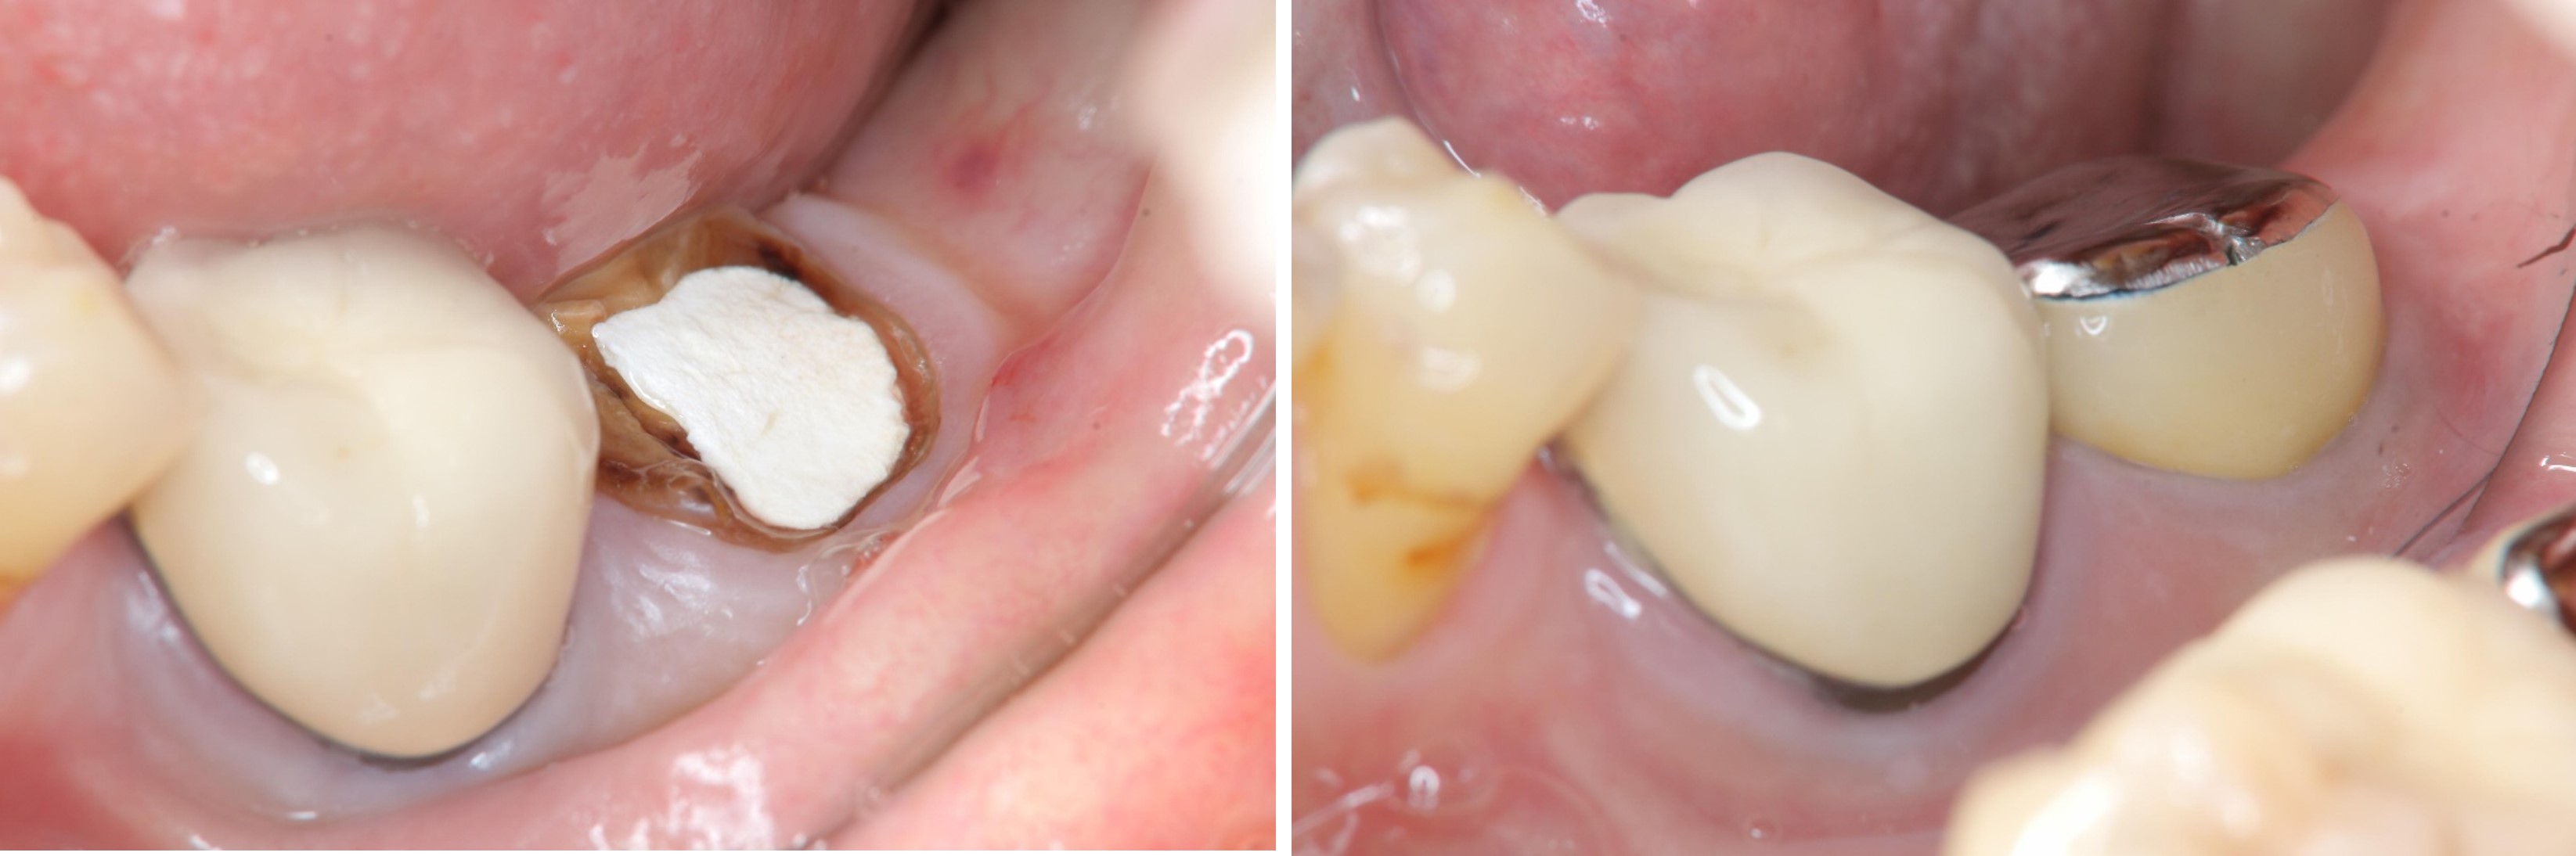

陶瓷冠蓋體-蛀牙-#46

審美牙科

瓷塊-冠蓋體

陶瓷冠蓋體-二次蛀牙-#46